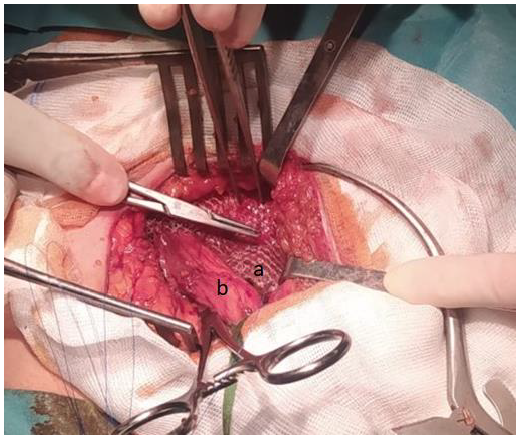

Within 48 hours after PD initiation, the patient presented with acute right-sided scrotal edema. CT-peritoneography was performed and revealed the recurrence of a right IH due to leakage of persistent dialysate fluid through a PPV (Figure 1).

Figure 1.Figure 1. CT-peritoneography with 3D reconstruction showing genital leakage associated with right PPV.